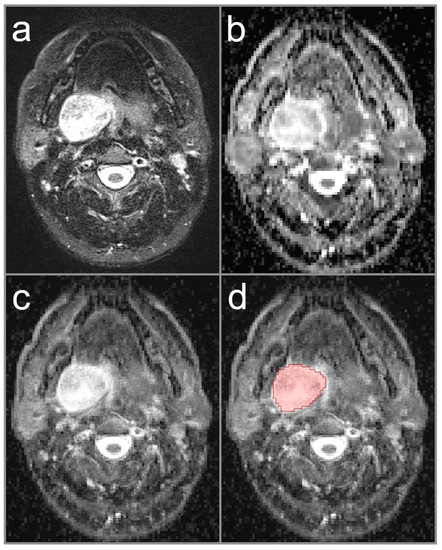

2.3. Image Analysis and ADC Measurement